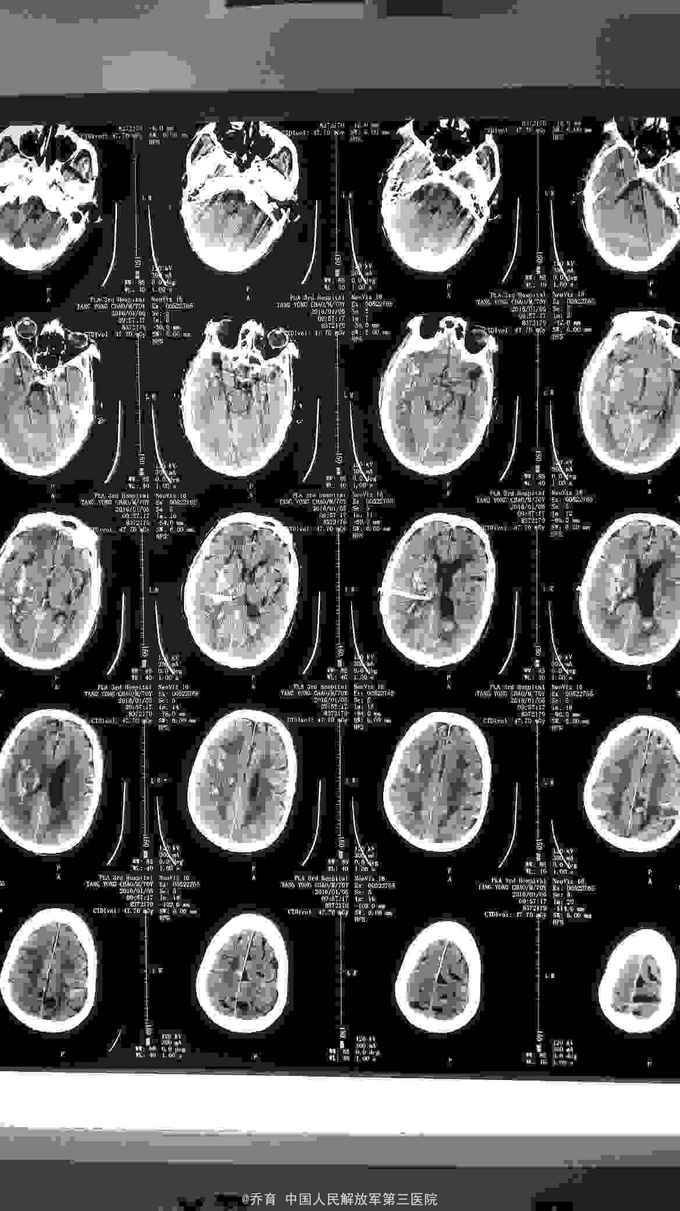

突发意识不清25小时入院,颅脑CT提示右侧基底节脑出血,量约35ml,左侧基底节区脑软化。胸部CT提示慢支,肺气肿,肺大泡,双下肺感染伴纤维化。

患者入院后急诊局麻下行脑内血肿穿刺引流术,术后给予止血,化痰,营养神经,营养支持等治疗。术后第二天复查CT提示出血大部分引出。